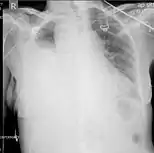

| Chest X-ray showing left sided hemothorax (arrowed) | |

A hemothorax (derived from hemo- [blood] + thorax [chest], plural hemothoraces) is an accumulation of blood within the pleural cavity. The symptoms of a hemothorax may include chest pain and difficulty breathing, while the clinical signs may include reduced breath sounds on the affected side and a rapid heart rate. Hemothoraces are usually caused by an injury, but they may occur spontaneously due to cancer invading the pleural cavity, as a result of a blood clotting disorder, as an unusual manifestation of endometriosis, in response to Pneumothorax, or rarely in association with other conditions.

Hemothoraces are usually diagnosed using a chest X-ray, but they can be identified using other forms of imaging including ultrasound, a CT scan, or an MRI. They can be differentiated from other forms of fluid within the pleural cavity by analysing a sample of the fluid, and are defined as having a hematocrit of greater than 50% that of the person's blood. Hemothoraces may be treated by draining the blood using a chest tube. Surgery may be required if the bleeding continues. If treated, the prognosis is usually good. Complications of a hemothorax include infection within the pleural cavity and the formation of scar tissue.